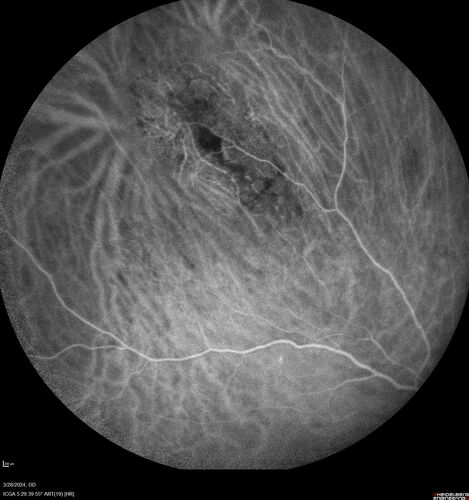

Serous Macular Detachment from Small Choroidal Melanoma

72 year old female misdiagnosed as CSR who had small choroidal melanoms.